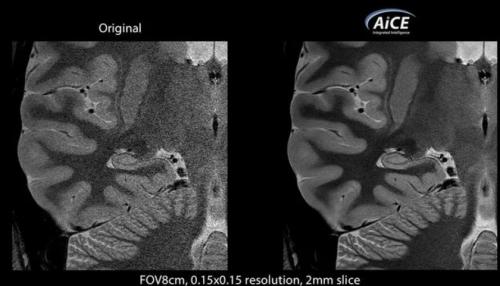

AICE 可以使用深度学习算法区分 Vantage Galan 3T 磁共振设备中真实的 MR 信号和噪声,从而实现增强 MR 图像的同时抑制噪声。

输出更高质量图像,AICE 通过深度学习技术区分 MR 设备和 CT 设备中的真实信号和噪声,在不增加辐射剂量同时,减少噪音对图像分辨率的影像,保持解剖学真实结构。

在临床双盲试验中,医生普遍认为应用 AICE 技术的 MR 重建图像,相比于传统常规 MR 重建图像,在分辨率和清晰度上都要更胜一筹。